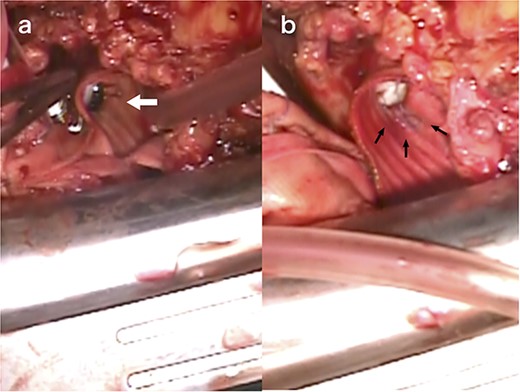

During reoperation, the right femoral artery and vein were cannulated to institute the cardiopulmonary bypass and cool the patient down to 28°C. After re-sternotomy, bleeding was observed in both coronary buttons, with a large haematoma surrounding the artificial vessels. The ascending aortic graft was cross-clamped and myocardial protection was achieved through antegrade cardioplegia. After transverse incision of the artificial vessel, we observed remodeling of the aortic walls of the left and right coronary buttons, which had thinned since the previous surgery. Dehiscence was observed in the 6–9 o’clock thread of the left coronary button with no cutting of the aortic wall (Fig. 3a). Both the left and right coronary artery threads were loose (Fig. 3b), necessitating ligation with prior and additional sutures. The transverse incision of the artificial graft was closed, and the aortic clamp was released. The patient was extubated on the day after surgery and discharged on the 10th postoperative day.

Intraoperative view of reoperation. The arrow indicates the dehiscence in the 6–9 o’clock thread of the left coronary button (a). The arrow indicates the loose thread (b).